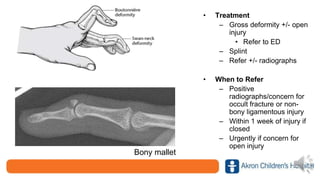

Non-bony mallet

• Treatment

– Gross deformity +/- open

injury

• Refer to ED

– Splint

– Refer +/- radiographs

• When to Refer

– Positive

radiographs/concern for

occult fracture or non-

bony ligamentous injury

– Within 1 week of injury if

closed

– Urgently if concern for

open injury

Bony mallet